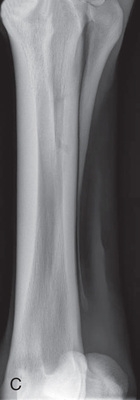

| Metacarpal/metatarsal cannon bone (M3) | Dorsoproximal-palmarodistal (DPr-PaDi) | Dorsopalmar (DP) |

| Lateromedial (LM) | Lateral (L) | |